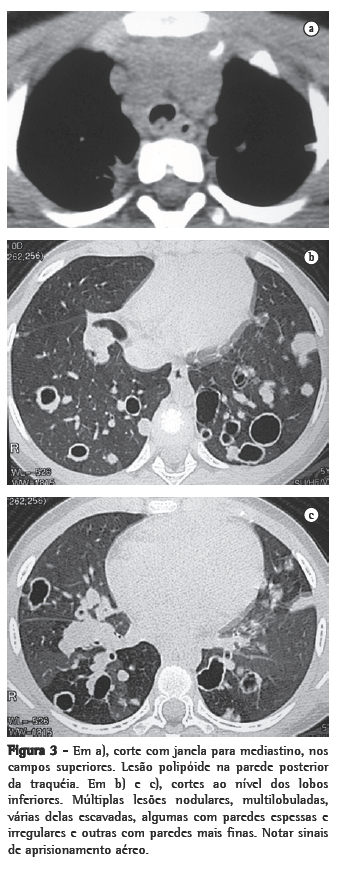

Nos 8 casos foram observadas na TC formações polipóides na traquéia. Em 1 deles, identificou-se também uma lesão em brônquio principal. Sete pacientes mostravam comprometimento do parênquima pulmonar. Em todos foram observadas lesões nodulares escavadas, com contornos internos irregulares, e paredes de espessuras variadas, com aspecto multilobulado em 6 casos, e com confluência das lesões em 5 deles (Figuras 1 a 5). Nódulos sólidos foram vistos em 6 pacientes, Em apenas 1 dos casos foram vistos níveis líquidos. As lesões predominaram nas bases em 3 pacientes, nos terços médios em 2, e em 2 não havia predomínio de distribuição. Em 1 dos pacientes, foi observada associação com massa, e em outro, com consolidação. Neste último paciente (Figura 5) foi constatada degeneração maligna em múltiplas lesões. Sinais de aprisionamento aéreo também foram observados em 1 caso. Em nenhum deles detectou-se linfonodomegalia ou derrame pleural.

A TC, particularmente com aquisição volumétrica (espiral), é superior às radiografias de tórax no reconhecimento de nódulos ainda pequenos, nas fases iniciais de disseminação pulmonar, por sua melhor caracterização e visualização de vegetações nodulares traqueobrônquicas. Os achados tomográficos incluem estreitamento nodular, focal ou difuso, da via aérea. Os nódulos crescem na superfície mucosa, e sua extensão intraluminar é melhor avaliada por TC.(3) São alterações facilmente correlacionadas à doença quando se dispõe da história clínica de papilomatose.(4) Outros achados relacionados à obstrução das vias aéreas e/ou infecções associadas são atelectasias, consolidações, aprisionamento aéreo e bronquiectasias.(2-4) Na nossa casuística, formações polipóides na traquéia foram observadas em todos os exames tomográficos. Sete pacientes mostravam comprometimento do parênquima pulmonar, caracterizado por lesões nodulares escavadas, com contornos internos irregulares, e paredes de espessuras variadas, com aspecto multilobulado e tendendo à confluência. Nódulos sólidos foram vistos em 6 pacientes. Em nenhum deles detectou-se linfonodomegalia ou derrame pleural.